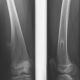

не экзофит, а костно-хрящевой экзостоз! имеет смысл поискать еще...

Самый, что ни на есть, настоящий экзостоз.

Был направлен именно на "экзофит?". Со слов ребенка впринципе ни чего подобного его не беспокоит.